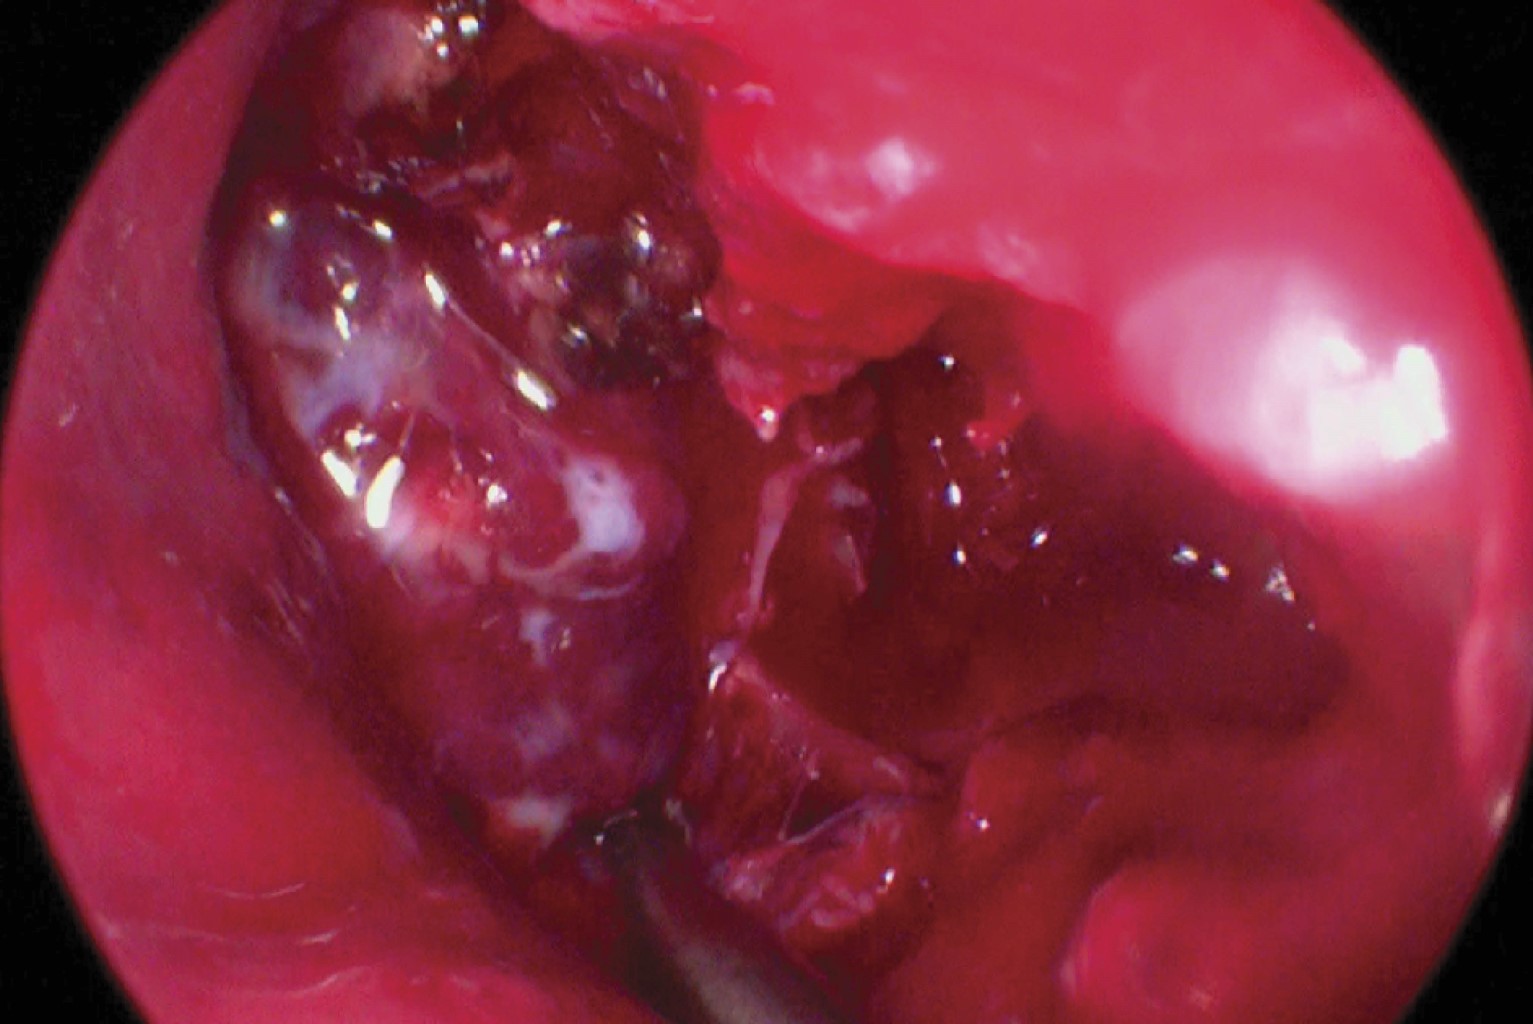

Se extirpa parcialmente el cornete inferior y medio; se diseca la pared lateral de la cavidad nasal izquierda y se efectúa una maxilectomía parcial con motor eléctrico y fresa de diamante, eliminando la pared medial y posterior del seno maxilar (Figuras 6 y 7).

La disección del tumor se realizó de manera centrípeta, dirigiéndolo hacia cavidad oral en la cual se termina disecando y extrayendo el tumor por medio de la cavidad oral al exponerlo a la orofaringe. El tumor es enviado a estudio histopatológico (Figuras 8 y 9).

Figura 7

Figura 8